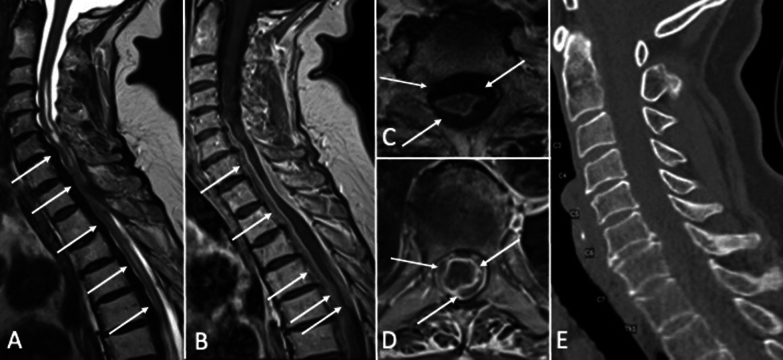

Immunoglobulin G4 (IgG4) related hypertrophic pachymeningitis of the spinal cord is a rare condition, characterized by infiltration of the spinal meninges with IgG4-producing plasma cells and subsequent hypertrophic fibrosis. Here, we report on a 65-year-old woman with IgG4 associated hypertrophic spinal pachymeningitis, in whom cerebrospinal fluid (CSF) analysis was a decisive diagnostic tool. Not only could we demonstrate an intrathecal IgG4 production, but also IgG4 positive plasma cells in CSF. Following decompressive surgery, diagnosis of IgG4 associated hypertrophic pachymeningitis was confirmed histologically. Surgery and immunosuppressive therapy with rituximab were associated with clinical improvement. This case highlights CSF analyses as diagnostic tool for detection of IgG4 related hypertrophic pachymeningitis.